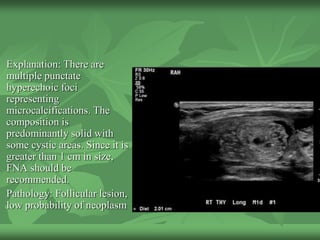

Explanation: There are

multiple punctate

hyperechoic foci

representing

microcalcifications. The

composition is

predominantly solid with

some cystic areas. Since it is

greater than 1 cm in size,

FNA should be

recommended.

Pathology: Follicular lesion,

low probability of neoplasm